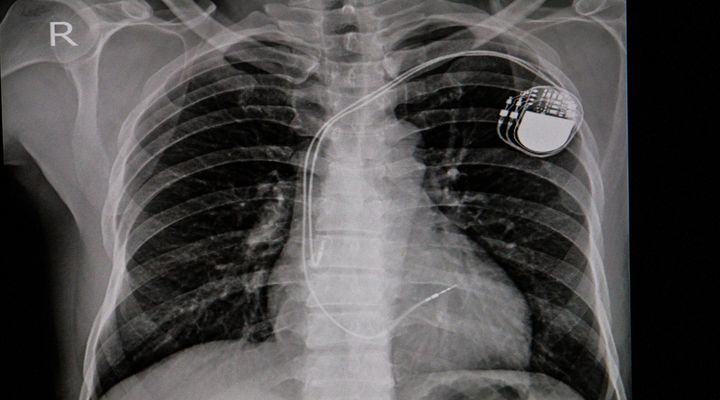

Doctors ended up discovering that Jill had a congential condition that was unknown. This condition is what caused her heart to stop beating int he first place and led to her going into a coma.

Out Of Her Coma

Jill had come out of her coma and was breathing on her own. By a miracle of God, she underwent surgery to implant a pacemaker for her heart condition and then went into a rehabilitation center.